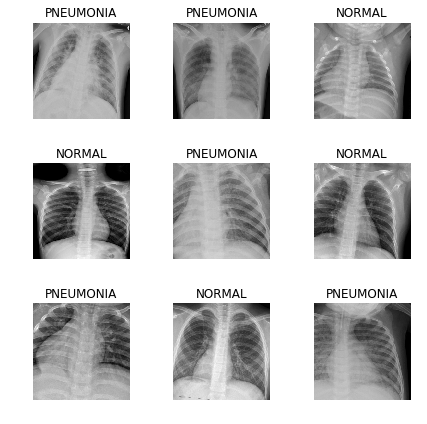

Заглянем в данные:

data.show_batch(rows=3, figsize=(6,6))